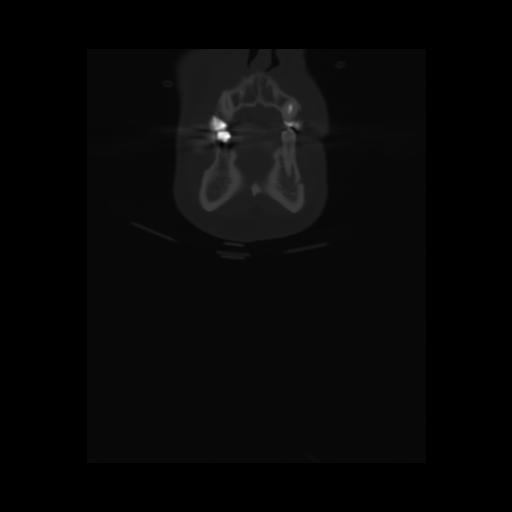

13 P.BLANDAS,,Coronal,2.000,P.BLANDAS,Coronal,